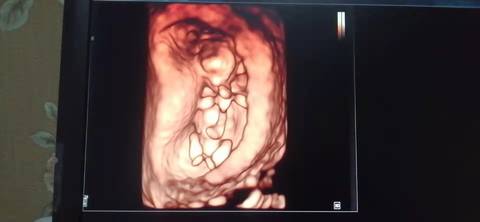

十二周的nt,是不是小棉袄啊? 医生给看宝宝腿的时候生殖器那里是平平的,是女宝吗?我和老公都挺想要小棉袄的

journal_insert_pic_1741079415journal_insert_pic_1741079899journal_insert_pic_1741080145journal_insert_pic_1741080277